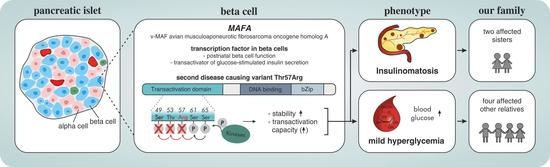

Second MAFA Variant Causing a Phosphorylation Defect in the Transactivation Domain and Familial Insulinomatosis

:Simple Summary

Abstract

1. Introduction

4. Discussion

5. Conclusions